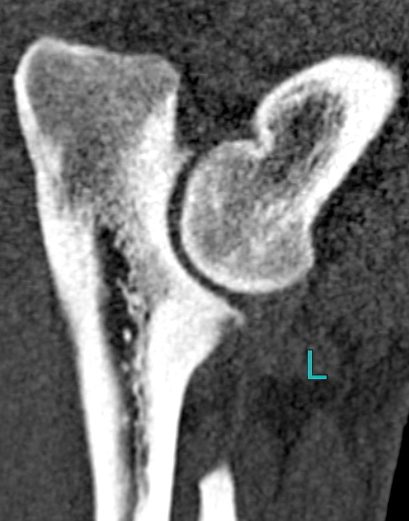

- I really don’t know what we’re looking at on this part of the ct scan. Other than it’s Pasha’s left.

While Pasha happily slipped back into a nap to my petting and stroking, the doctor showed me the scan and gave me his analysis of the imagery. To my astonishment, he said he’s seeing a ‘rather good’ set of shoulders and elbows (!), nothing in the way of arthritis (!!), and basically nothing in the way of elbow dysplasia (!!!). He did point to the same areas where our regular vet had diagnosed signs of elbow dysplasia and Fragmented Coronoid Process (FCP) out, but this doctor wiped them off the table as “nitpicking”. Well, insert dumbfounded look here. Our regular vet, who developed himself into a fine specialist surgeon for movement problems over the years, will probably still be on a well-deserved holiday break when I publish this article but I can hardly wait to discuss this scan with him! He’s the vet who made the x-rays in 2016 and last month and who called for arthritis/elbow dysplasia as a tentative diagnosis. I also still don’t have the radiologist’s second opinion at this point, which I’m equally curious about. Anyway, both the doctor and I swiftly moved on to this question: if Pasha has indeed good shoulders and elbows, than what is ailing him? The doctor reasoned it could very well be something in the softer tissues. Think a strained muscle or maybe a tear in a tendon or something. This sure sounded logical to me, but in the back of my head, I also thought about the back and neck hernias Misha and Bromley were diagnosed with during a previous life…